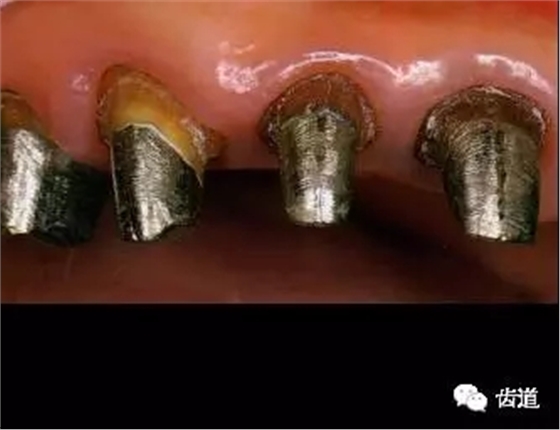

二)確認(rèn)在代型上完全就位:

全冠僅邊緣與代型接觸,其余內(nèi)表面與代型表面間隙大小為30-40μm。

四)人造冠就位 1、理論標(biāo)志

人造冠內(nèi)表面與患牙面間隙不大于50μm。 2、參考標(biāo)志